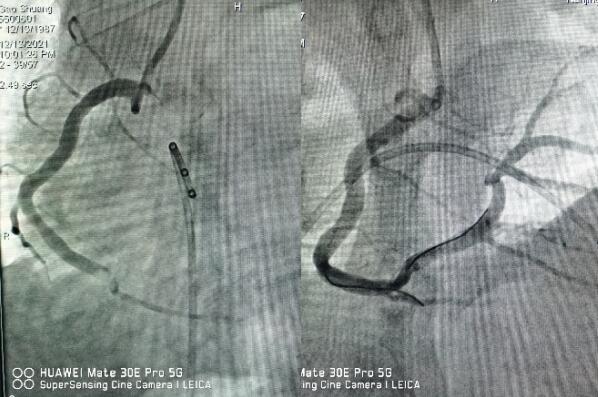

醫(yī)生立即予以搶救,并第一時間通知心內(nèi)科值班醫(yī)師,緊急啟動綠色通道,全院相關(guān)科室全力配合,心內(nèi)科介入團隊分工明確,迅速啟動導(dǎo)管室。因患者心梗后并發(fā)嚴重心律失常,為了安全起見,造影前植入臨時起搏器,造影提示右冠狀動脈急性完全閉塞,并成功開通血管,患者胸痛即刻緩解,目前正在康復(fù)過程中。